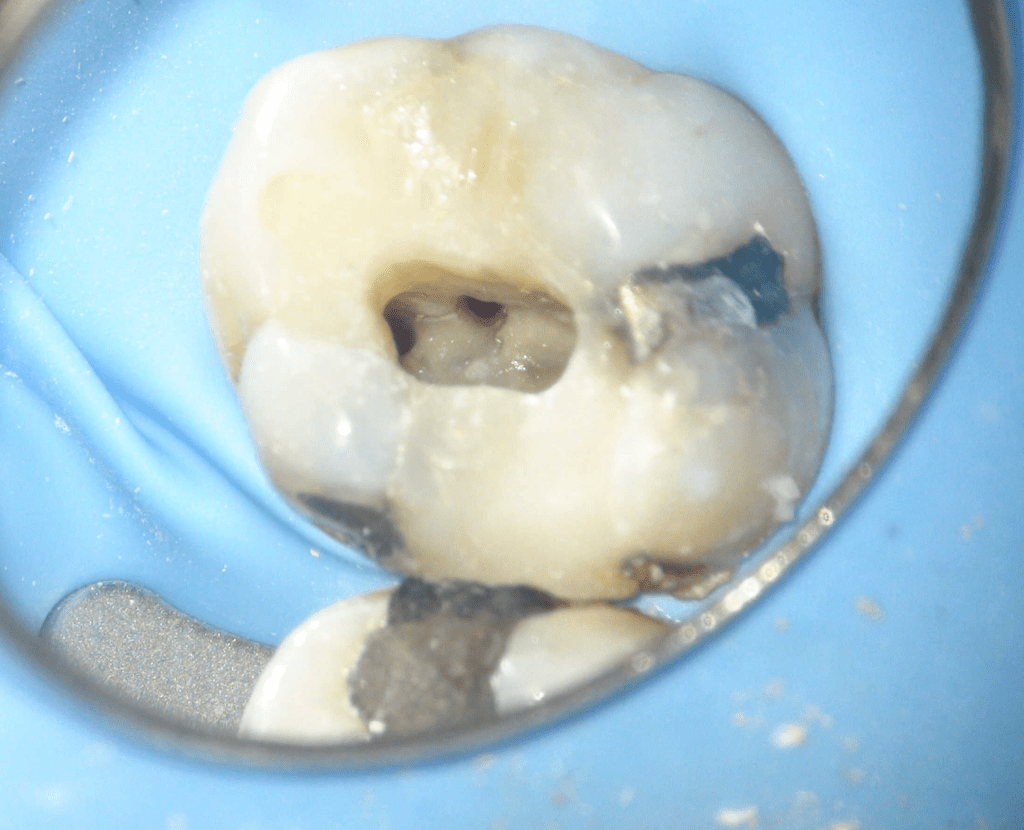

Molar superior

Reco preendo + 4 conductos molar superior